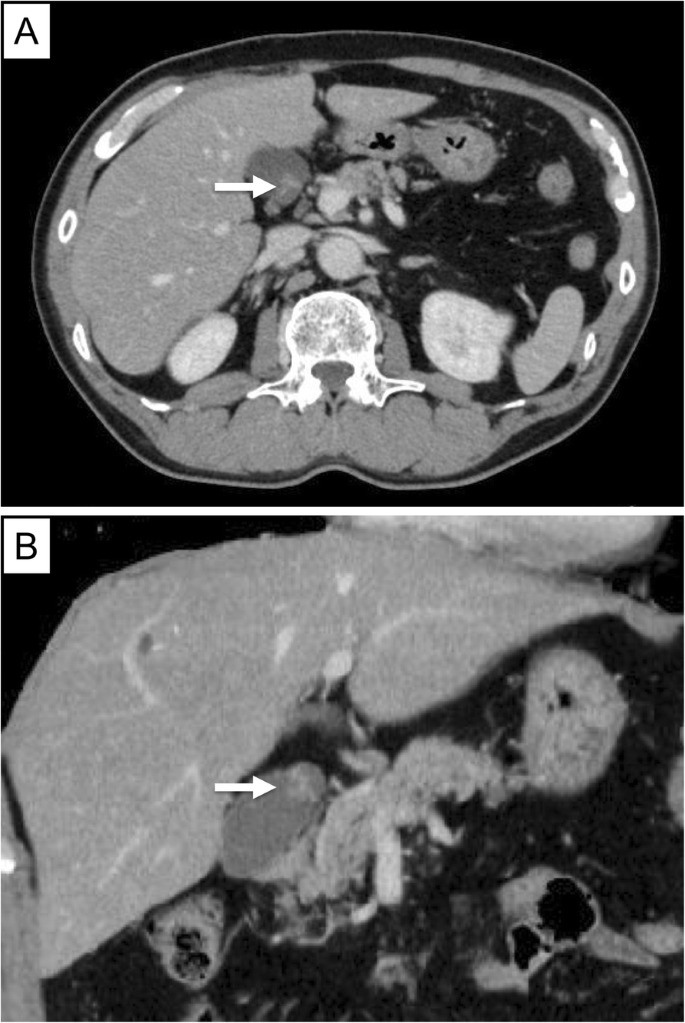

A 10-mm pedunculated polyp in the gallbladder neck was detected on a follow-up abdominal ultrasound in a 60-year-old man with chronic hepatitis and hepatitis B without medication. A benign tumor or low-grade malignancy was suspected, and he initially did not wish to undergo surgical resection. Six months later, an abdominal ultrasound showed an increase in the polyp to 12 mm at the neck of the gallbladder with point-like perfusion, focal thickening of the gallbladder wall, and a gallbladder stone at the fundus (Fig. 1). Enhanced computed tomography (CT) scan (Fig. 2) and magnetic resonance imaging (MRI) (Fig. 3) revealed a polypoid lesion at the neck of the gallbladder, a distended gallbladder with a thickened and enhanced wall, and a gallbladder stone at the fundus. He was asymptomatic, and laboratory examinations revealed that the patient had a normal liver function and coagulation with hepatitis B virus DNA level of 3.2 log IU/ml; positive and negative serologic markers for hepatitis B envelope antibody and envelope antigen, respectively, and the tumor marker levels were within normal ranges [carcinoembryonic antigen, CEA (1.8 U/ml; normal range < 5.0 U/ml) and CA19-9 (9.9 U/ml; normal range < 37 U/ml)]. Although the patient was diagnosed with a benign gallbladder polyp, malignancy could not be completely excluded. Therefore, a laparoscopic cholecystectomy was performed. Intraoperatively, only a slight thickening of the gallbladder wall was detected. Macroscopically, there was a pedunculated yellowish polyp (14 × 11 × 15 mm) at the neck of the gallbladder. The gallbladder wall was thickened, and the Rokitansky-Aschoff sinus (RAS) was clustered at the wall (Fig. 4a).

Due to the lack of specific findings on the CT scan or MRI, it is difficult to diagnose gallbladder NEN preoperatively. Gallbladder NEN is often misdiagnosed as a benign tumor, i.e., cholesterol polyp or adenoma prior to surgery. If the diagnosis of gallbladder NEN was made preoperatively, we should have considered operative methods such as local excision, radical resection, and lymphadenectomy. Previous research recommends that local excision without lymphadenectomy should be carried out for NET G1 tumors less than 2 cm in the stomach, duodenum, appendix, and rectum. Lymphadenectomy is recommended for other gastroenteropancreatic NENs in the jejunum, ileum, colon, and pancreas [9, 11]. Although the risk of metastasis depends on the tumor size in several gastroenteropancreatic NENs, the risk factors for metastasis of gallbladder NEN have not been clarified because only a small number of cases have been reported [11]. Previous NET research reported that the frequency of metastases was two of seven cases (28.6%) for tumors less than 1 cm, while all five cases with tumors measuring 3 cm or more had metastases. This research indicated that tumor size is a possible risk factor of metastases for gallbladder NEN [12]. Frequent sites of metastatic lesions were the liver (91.7%), lungs (33.3%), lymph nodes (33.3%), bone (25%), and adrenal glands (25%) [8,9,10,11,12]. Only one case of gallbladder NET G1 less than 1 cm had lymph node metastasis [8]. MRI is a useful tool in staging gallbladder tumors, and previous research revealed the high sensitivity rates for lymph node invasion on MRI (92%) [13]. Therefore, we elucidated the tumor size and lymph node metastasis on MRI preoperatively. Postoperatively, if NET G1 was incidentally identified in the gallbladder of a surgical specimen, reports suggested that a detailed pathological examination of the cystic duct node should be performed [8]. If lymph node metastasis is positive, a radical second resection with regional lymphadenectomy should be considered. In this case, a small tumor size (1.5 cm) and histological type (NET G1) were associated with a good prognosis without metastasis. In addition, preoperative MRI showed no evidence of lymph node metastasis.